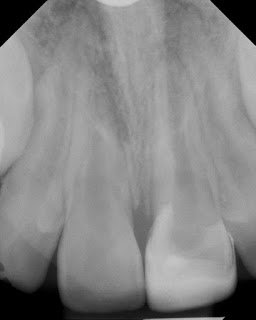

This young patient had a traumatic incident to tooth #9 5 months earlier. At our initial evaluation, the tooth responded normal to thermal testing. We decided to monitor the tooth over time. At a follow up visit, #9 exhibited no response to thermal testing with an open apex.